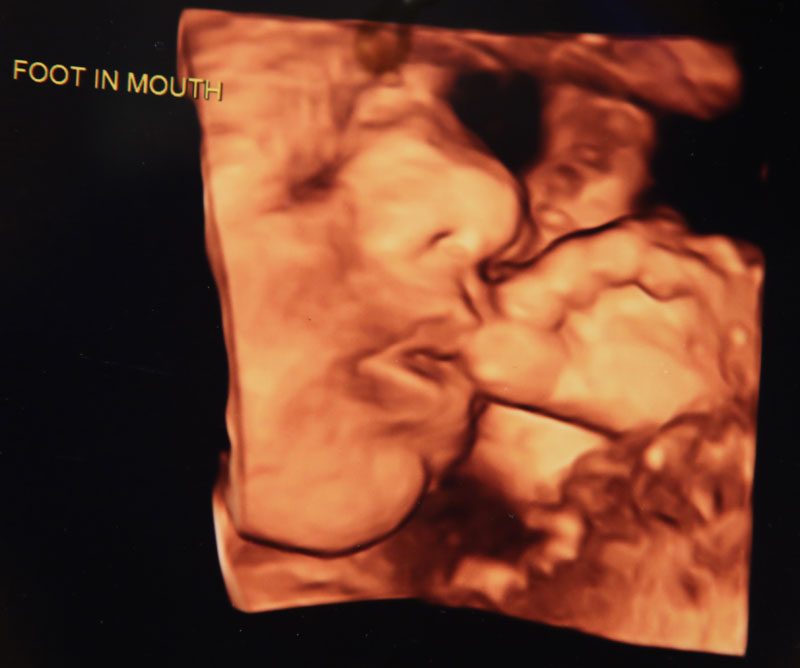

“At 20 weeks you see much more controlled movements,” Burnett said. “They are rolling, sucking their thumb, and their hands are constantly in their faces, especially when we are trying to analyze facial anatomy.”

She added that by 20 weeks she sees all kinds of hand movements including what appears to be baby waves and thumb-sucking.

“At 8 weeks they start wiggling, and at 12 to 13 weeks they start to open their hands,” said ultrasound tech Wendy Barberic.